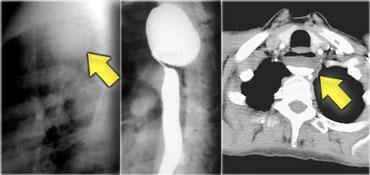

TRÁI: Thực quản giãn (mũi tên) biểu hiện là cấu trúc dài, bờ rõ nét song song với tim. PHẢI: Thực quản giãn thường lệch sang phải. Hẹp (mũi tên) tại khe hoành.

Achalasia

Hình ảnh chụp thực quản:

- Giãn thực quản kèm mất nhu động

- Hẹp thuôn nhẵn tại khe thực quản của cơ hoành

- Ung thư đoạn xa có thể giả dạng achalasia (giả achalasia)

TRÁI: CT cho thấy thực quản giãn (mũi tên) dẫn đến chỉ định chụp thực quản. PHẢI: Chụp thực quản cho thấy hẹp (mũi tên) tại mức khe hoành.